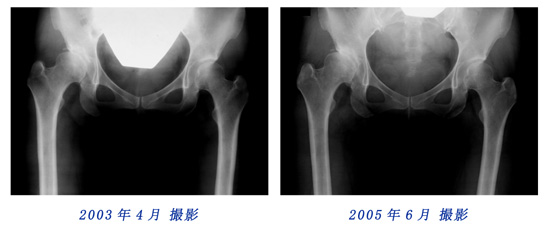

2000年6月と2003年4月のレントゲン写真を比較しても、変化は認めにくいのですが、2003年4月と2005年6月に撮影されたレントゲン写真の骨盤形状に顕著な変化を観察することができます。

比較用レントゲン写真

2003年4月と2005年6月に撮影されたレントゲン写真を重ねてみました。写真にカーソルを重ねると2003年と2005年の写真が入れ替わります。骨盤形状の変化を観察してください。